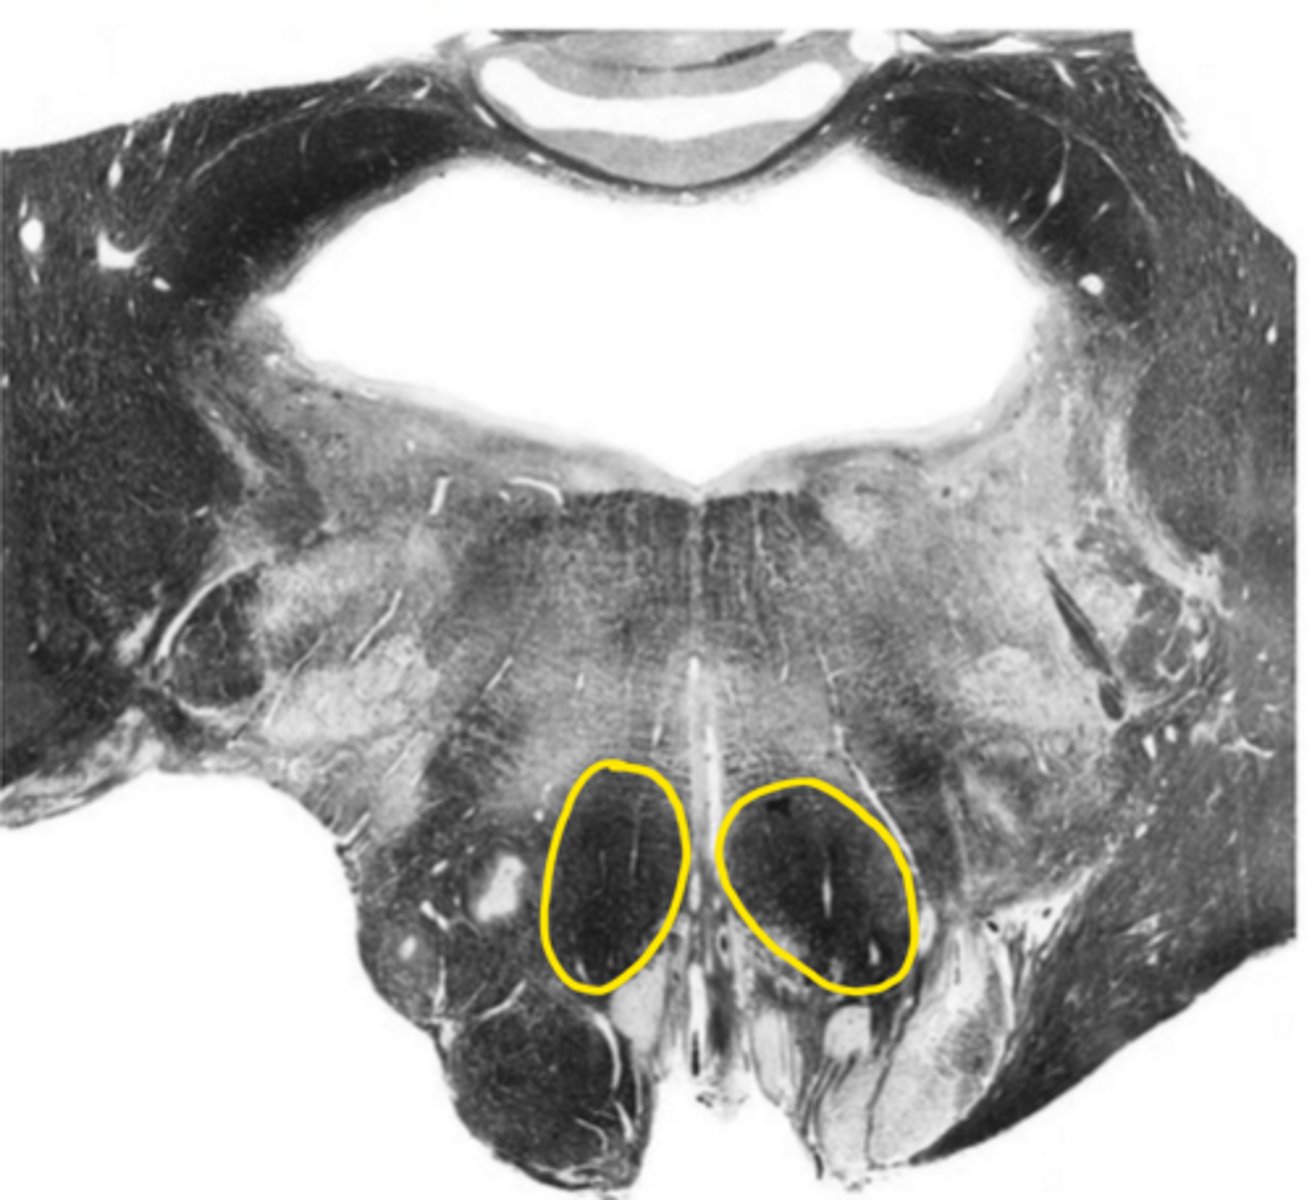

central canal

ID the space